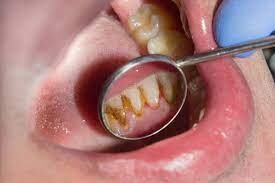

According to the IJDHS review, there are two types of dental calculus: supragingival and subgingival. The difference between the two types is the location of the calculus relative to the edge of the gum tissue.

If you think of the edge of the gums like a shirt sleeve and imagine the tooth is like your hand in the sleeve, you can get a better image of this classification. The parts of your hand and wrist that extend visibly outside the sleeve would be considered supragingival (above the gumline), whereas anything unseen below the sleeve would be considered subgingival (below the gumline). Calculus above the gumline can appear whitish or yellowish in color.

Removing Supragingival Calculus

While your dentist and dental hygienist can typically detect supragingival calculus visually, dental professionals also receive extensive training using equipment other than their eyes. One such example, according to the IJDHS review, is an instrument known as a dental explorer, which helps the dental professional feel and remove calculus. A scaler is another common handheld instrument used to remove calculus above the gumline, as a review in the Saudi Dental Journal notes. In addition to these, new technologies — such as ultrasonic and laser tools — have also emerged to help dentists and hygienists detect and remove calculus.

It's important to remove calculus as soon as it's detected to prevent further bacteria buildup and retain gum health. The ADA notes that as supragingival calculus develops, the gums can become swollen and bleed easily. This condition, termed gingivitis, can worsen into a more serious form of gum disease if left untreated.